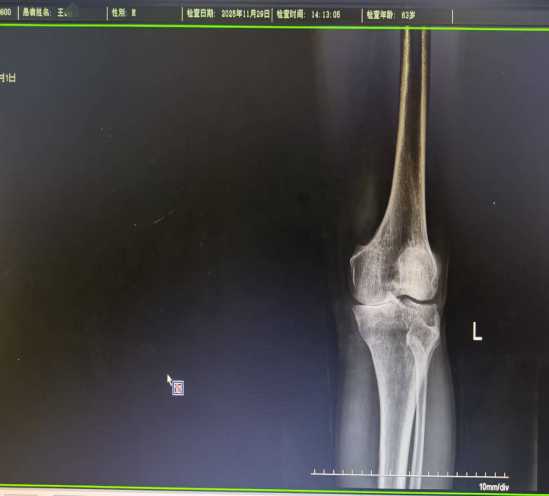

最近半年,膝盖的疼痛已严重影响到日常生活,连最基本的走路、上下楼梯都变得异常艰难。忍无可忍之下,王叔来到河南中医药大学附属郑州中医骨伤病医院,向创伤骨科董亚乐主任寻求进一步诊治。经详细检查,他被确诊为「双膝关节骨性关节炎」。

董亚乐主任在全面评估后,建议采用「单髁置换」这一微创手术方案来解除病痛。在与王叔及其家人充分沟通并取得同意后,手术如期进行。。